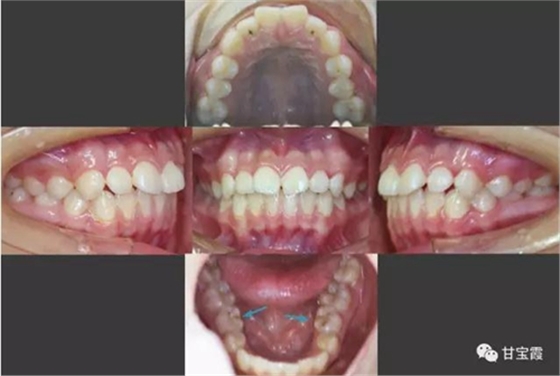

我有個朋友的小女孩前牙不齊、有點突,要求矯正。經(jīng)過臨床檢查和X診斷,發(fā)現(xiàn)先天缺失兩顆下頜第二雙尖牙。

于是我們決定拔出滯留的下頜乳牙和上頜的兩顆第一雙尖牙。

矯正中排齊并內(nèi)收上下前牙,同時也適當(dāng)?shù)那耙屏讼骂M后牙,關(guān)閉了所有的拔牙間隙,患者長大以后也不必要再鑲牙了。